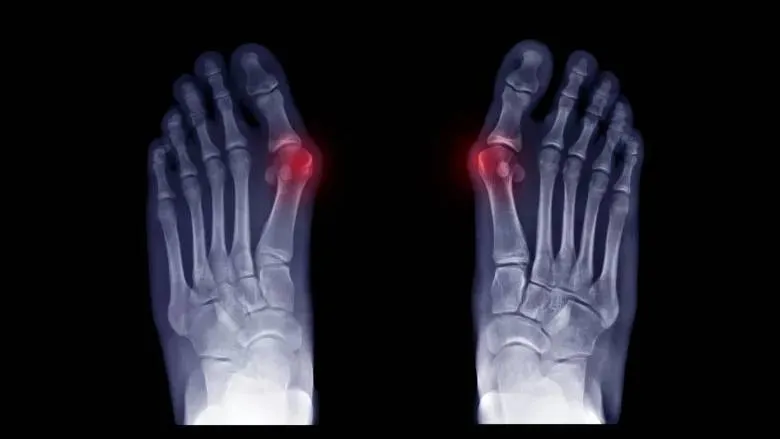

Vbočený palec napraví mini invazívne operácie. „Staršie operačné techniky často vedú k opätovnému rozvoju deformity,“ hovorí ortopéd.

Pacientov privádza k lekárovi najmä bolesti v oblasti predonožia. Pokiaľ sú bolesti spojené so zmenou postavenia palca alebo s obmedzením jeho hybnosti, tak je teda namieste navštíviť ortopedickú ambulanciu. Röntgenové snímky potom odhalia, v akom stupni sa ochorenie nachádza. Veľmi často sa stretávam s pacientkami, ktoré hovoria, že predonožie ich nebolí, pretože obmedzili fyzickú aktivitu. Tento prístup nie je ale správny, pretože fyzická aktivita je dôležitá pre správnu funkciu nohy a pokiaľ ju nevykonávame, tak sa stav zhoršuje.